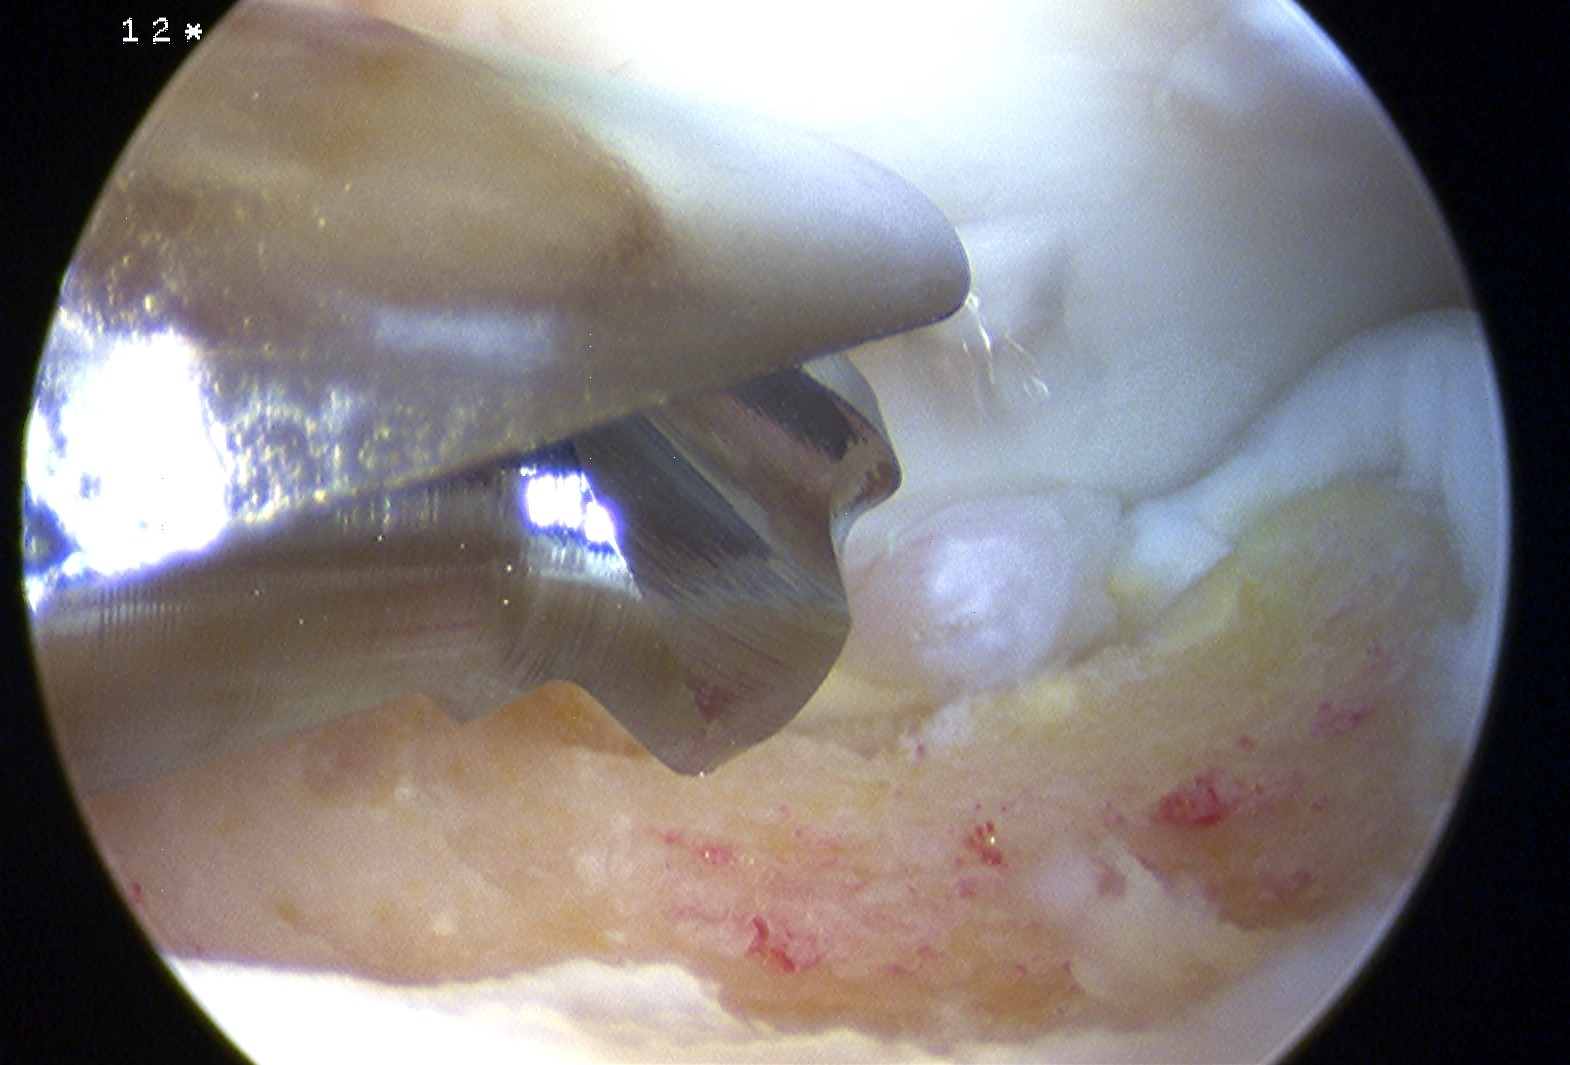

Microfracture

Technique

Arthroscopy techniques microfracture talus

- microfracture with collagen patch (Chondrogide) secured with fibrin glue